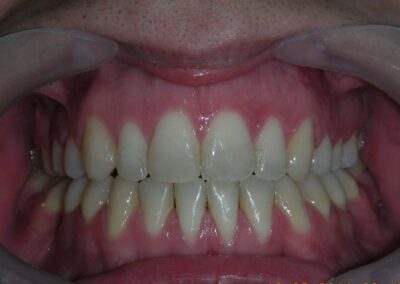

After two years of treatment using appropriate biomechanics, the overbite was successfully corrected from -8 mm to +1 mm, achieving complete closure of the anterior open bite without exacerbating the patient’s lower facial third vertical proportions. At this stage, occlusal contacts were verified using articulating paper, and functional movements of the canines and incisors were evaluated to ensure proper anterior guidance and disclusion patterns. The patient was then referred to speech therapy (myofunctional evaluation) as part of the pre-debond assessment protocol.

Finishing and Retention

At the completion of treatment (28 months) , the patient exhibited significant skeletal and dental improvements consistent with the initial treatment objectives. A reduction of 3 degrees in lower anterior facial height and a 4-degree increase in the facial axis angle were observed on post-treatment cephalometric analysis, indicating a favorable counterclockwise, anterior mandibular rotation. This skeletal change, in conjunction with the mesialization of posterior segments and space closure mechanics, led to the successful resolution of the anterior open bite. During the retention phase, a modified Hawley appliance was used in the maxillary arch, while the mandibular arch was stabilized with a fixed retainer made of twist-flex (supercable) wire #33 to #43 , which had been heat-treated to eliminate its elasticity. This retention strategy was complemented with myofunctional therapy, aimed at ensuring long-term neuromuscular stability.